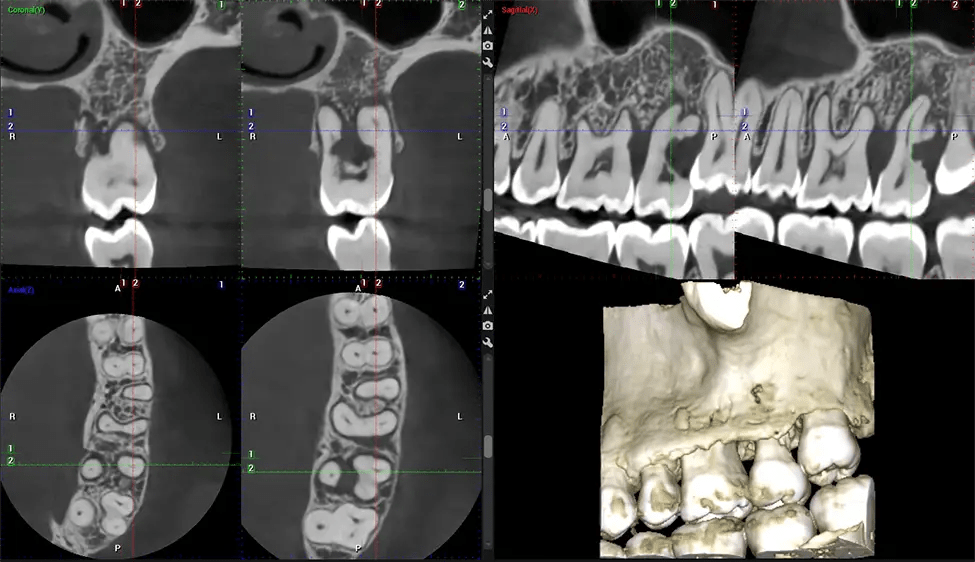

This 3D scan, called cone beam computed tomography, gives your dentist a more complete image of your oral anatomy and disease processes than a traditional X-ray. Unlike conventional X-rays, which capture a 2D image of your mouth from various angles, a 3D scan takes multiple digital X-rays for one image. It provides a complete view of your jaw, teeth, nerves, and soft tissues. This enhanced view allows dentists to detect minor issues not visible in traditional 2D scans, such as impacted wisdom teeth or bone fractures in the sinus cavity.

There are many benefits to using CBCT technology, especially compared to the traditional 2D X-ray format. One of the most significant advantages of CBCT scans is that they provide much more information than traditional X-rays. A scan lets your dentist see images from all angles of your jaw and mouth, including your sinuses, nasal cavity, cheekbones, and other surrounding areas. This added information helps your dentist craft a comprehensive treatment plan that addresses all aspects of your oral health.

Another significant benefit is that 3D imaging provides more precise images of your bone structure. These images are more detailed, providing you with a more accurate diagnosis. An accurate diagnosis means better treatment for you.

After the scanning process, the captured X-ray images are processed by the CBCT software, which applies algorithms to reconstruct a detailed 3D image of the scanned area. The software compiles these individual X-ray images and creates a digital 3D representation of the patient’s anatomy. The reconstructed 3D CBCT image can be viewed and analyzed by the dentist or radiologist. This image can be manipulated, rotated, and zoomed in or out to examine specific structures and evaluate the patient’s condition.